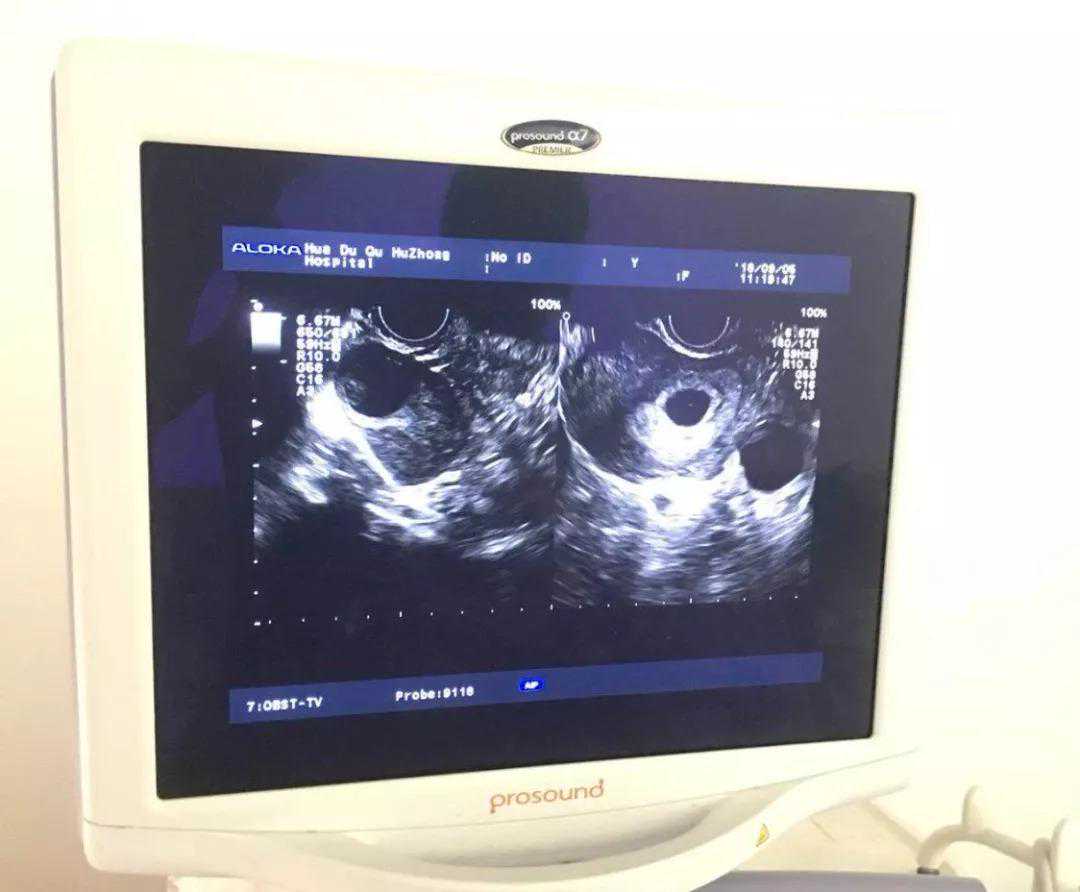

2018年7月,确定了促排卵方案,8月上旬进行胚胎移植,移植2周后验血确认成功受孕,移植4周后通过B超确定宫内妊娠。